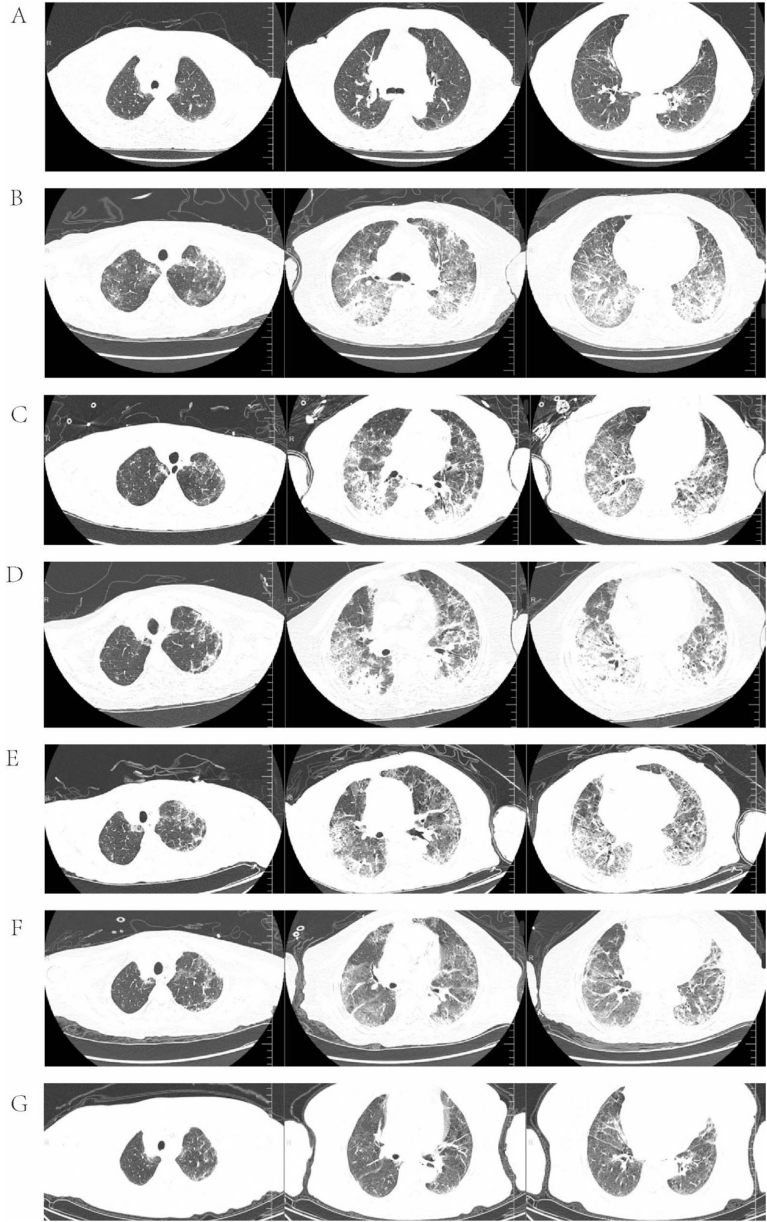

),但联合用药两次后即出现典型ILD影像学改变(

)。